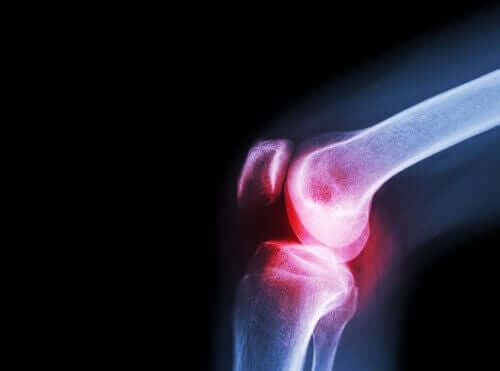

La polyarthrite rhumatoïde est une maladie inflammatoire chronique de nature auto-immune. Elle se caractérise par l’affection de nombreuses articulations et le développement de divers symptômes généraux et non spécifiques.

Si on ne la traite pas correctement, cette maladie peut entraîner d’importantes limitations physiques et aggraver considérablement la qualité de vie des patients.

En terme de symptômes, la polyarthrite rhumatoïde se manifeste généralement par des douleurs et une raideur ou des difficultés à mouvoir les différentes articulations, petites ou grandes.

Les symptômes généraux, qui précèdent parfois les manifestations articulaires et ont tendance à persister tout au long de la maladie comprennent, entre autres :

Toutefois, le premier symptôme le plus fréquent est la rigidité articulaire matinale. Surtout dans les pieds et les mains.